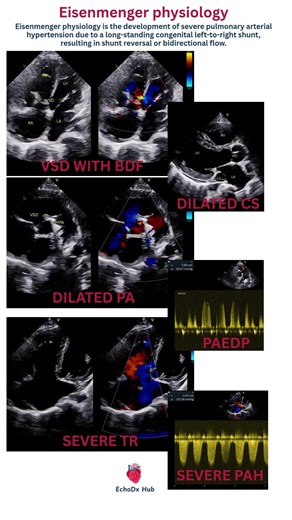

TR in 2 D Echo - Apical Aneurysm